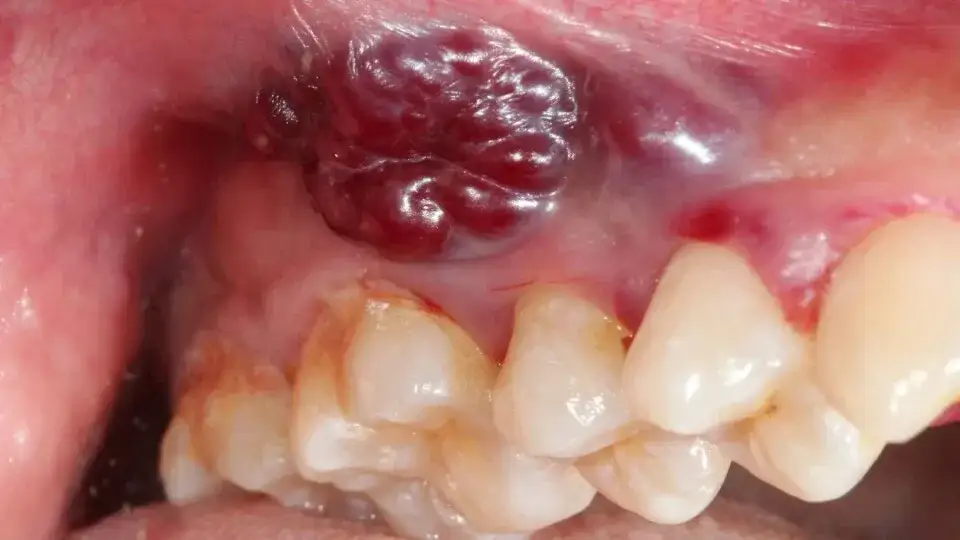

Zwróćmy także uwagę na guz lub zgrubienie w obrębie jamy ustnej na języku, wardze, dziąśle czy policzku. Może być twardy, miękki, ruchomy lub unieruchomiony. Choć nie każdy guzek jest złośliwy, każdy wymaga oceny lekarskiej. Pamiętam pacjentkę, która przez miesiące ignorowała małe zgrubienie na języku, myśląc, że to afta. Okazało się, że był to wczesny rak.

- Oglądanie wnętrza policzków i dziąseł: Odciągnij policzki, aby dokładnie obejrzeć ich wewnętrzną stronę oraz dziąsła. Zwróć uwagę na białe, czerwone lub ciemne plamy, owrzodzenia, guzki czy obrzęki.

- Oglądanie języka (góra, boki, spód): Wysuń język i obejrzyj jego górną powierzchnię. Następnie, używając gazy lub chusteczki, delikatnie chwyć koniec języka i wysuń go na bok, aby obejrzeć boki języka. Na koniec unieś język do góry, dotykając nim podniebienia, aby obejrzeć jego spód i dno jamy ustnej. Szukaj wszelkich zmian w kolorze, teksturze, guzków, owrzodzeń czy trudności w poruszaniu językiem.